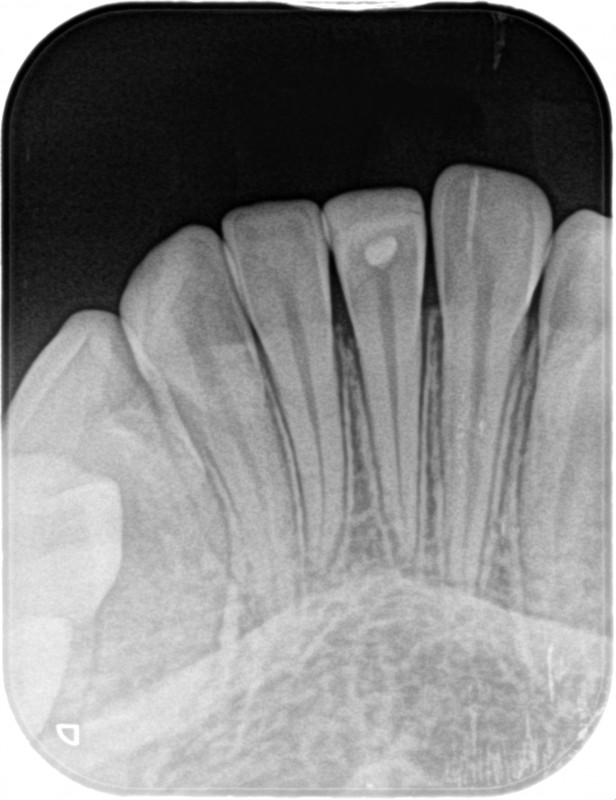

前歯が外傷で破折、神経が露出していましたが、ダイレクトボンディングで修復したケースです。

神経が露出しています。

このようなケース、一般的には神経を取ってかぶせ物を入れる治療になると思いますが、神経を取ると歯の寿命は短くなります。

このケースでは、神経を取らずに保存し、詰め物で修復することにしました。

MTAセメントで神経を保護します。

その上をダイレクトボンディングで修復しました。

ラバーダムを外して完成です。

神経を保存して、詰め物で修復することにより、極めて低侵襲な治療をすることができました。